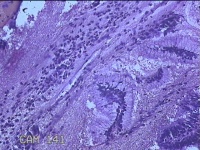

性别

女

年龄

44岁

临床诊断

子宫异常出血;子宫肌瘤;子宫内膜息肉

一般病史

阴道流血1月。

标本名称

宫颈管内膜

大体所见

纱布一块,内有灰白暗红色不规则碎组织1.5x1x0.2cm一堆。

图2